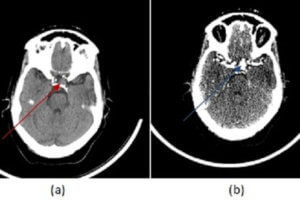

Dense MCA sign in R hemisphere

Early Signs of Stroke on CT

Despite its poor sensitivity for detecting embolic strokes, head CT scan remains the initial imaging modality in the work up of suspected acute stroke. The rationale is to initially rule out hemorrhagic... Read more »